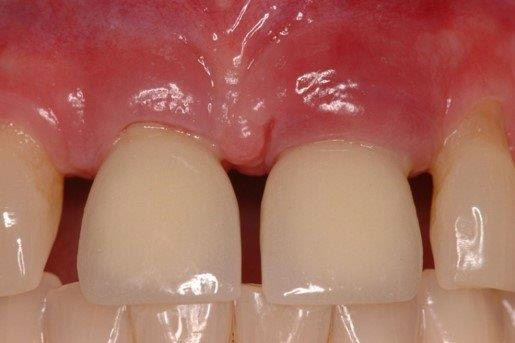

Figure 2

radiograph illustrating peri-implantitis (courtesy of Dr. Liran Levin)